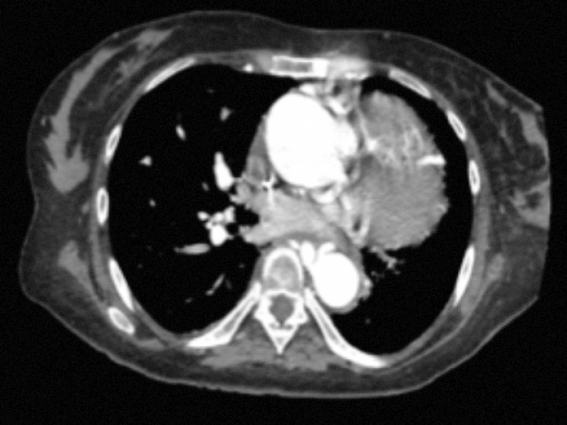

negativos, y una angio-TAC de tórax que demuestra asimetría en la

vascularización pulmonar, menor en el lado izquierdo, áreas de mosaico con atenuación

en ambas bases pulmonares, engrosamiento de septos inter- e intralobulillares,

más evidentes en el pulmón izquierdo, opacidades micronodulares en el lóbulo

superior izquierdo, de localización periférica; no se identifica el tronco de

la arteria pulmonar ni ramas pulmonares confluentes; a nivel cardíaco se

aprecia cardiomegalia e hipertrofia a expensas de las cavidades cardíacas

derechas, y se observa un defecto amplio en el septo interventricular de tipo

perimembranoso compatible con comunicación interventricular de aproximadamente

31 mm de diámetro (Fig. 1). Adicionalmente, en un ecocardiograma transesofágico

Figura 1. Angio-TAC

de tórax que muestra cardiopatía congénita tipo atresia pulmonar sin

identificación de ramas pulmonares confluyentes con comunicación

interventricular y marcada hipertrofia del ventrículo derecho, especialmente

hacia la región infundibular.